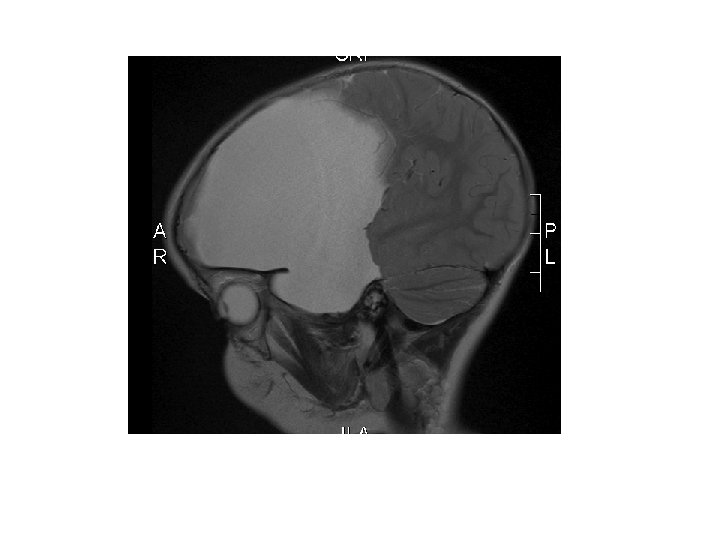

Greining • CT • MRI • Ísótóparannsóknir • Einkennalaust: Greinist oft fyrir tilviljun með CT eða MRI • Einkenni: Gullstandard MRI

Heilaskúmsbelgir - Arachnoid cysts • Skilgreining: – Heila- og mænuvökvafylltir belgir, þaktir heilaskúmsfrumum og kollageni, sem geta myndast á yfirborði heilans, innan heilans eða í mænunni.